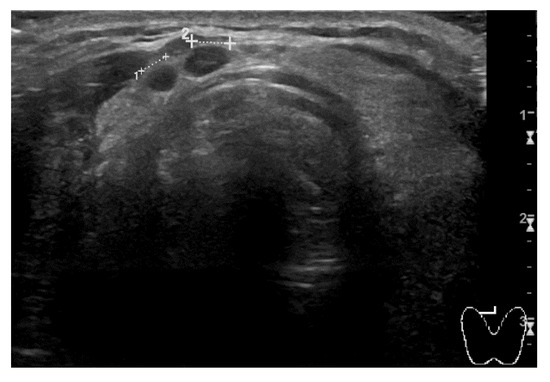

The second clinical case regards a man who was diagnosed with RCC of the left kidney. He first underwent partial nephrectomy in 2015. Two years later, radical nephrectomy was performed due to locoregional recurrence. At the follow-up CT scan of March 2021, right kidney and multiple lung metastases were detected. The prognosis was scored as a ‘favorable risk’ group according to the IMDC algorithm. The patient was 64-year-old at the time and his only significant comorbidities were hypertension and diabetes mellitus type II, both pharmacologically controlled by atenolol, linagliptin, and metformin. The patient was provided with comprehensive information and first-line therapy with three-weekly pembrolizumab 200 mg; axitinib 5 mg bid was promptly started. After two cycles of treatment, blood pressure values were no longer under control with the usual therapy, and the man started complaining about new onset G2 fatigue. Blood pressure control was rapidly achieved by adding amlodipine to the usual therapy and temporarily discontinuing axitinib for one week. Later, the patient noticed a left lateral-cervical swelling area of new appearance. A neck ultrasound (US) examination was performed, and it revealed multiple thyroid nodules consistent with toxic goiter (Figure 4). No thyroid hormone alterations were detected on blood tests, thus no specific action has been necessary.

Figure 4. Immunotherapy-related thyroiditis on neck US examination. The thyroid gland is enlarged and swollen; uneven tissue pattern and nodular areas of phlogistic infiltrate are visible.